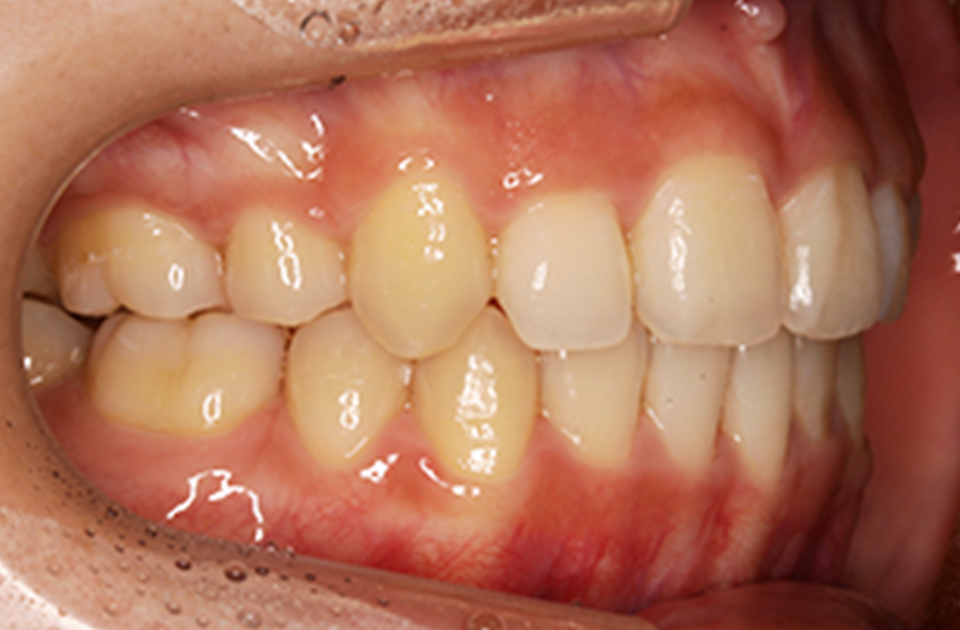

矯正後

矯正後 右側

主訴 前歯で物が咬めない、歯並びの凸凹、出っ歯を治したい

年齢 20代

治療法 上下顎マルチブラケット装置、歯科矯正用アンカースクリュー

抜歯の有無 上顎左右側第一小臼歯、下顎左右側第二小臼歯

治療期間 1年10ヶ月